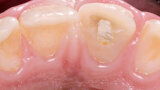

Endodontické ošetření horního středního řezáku s atypickou anatomií